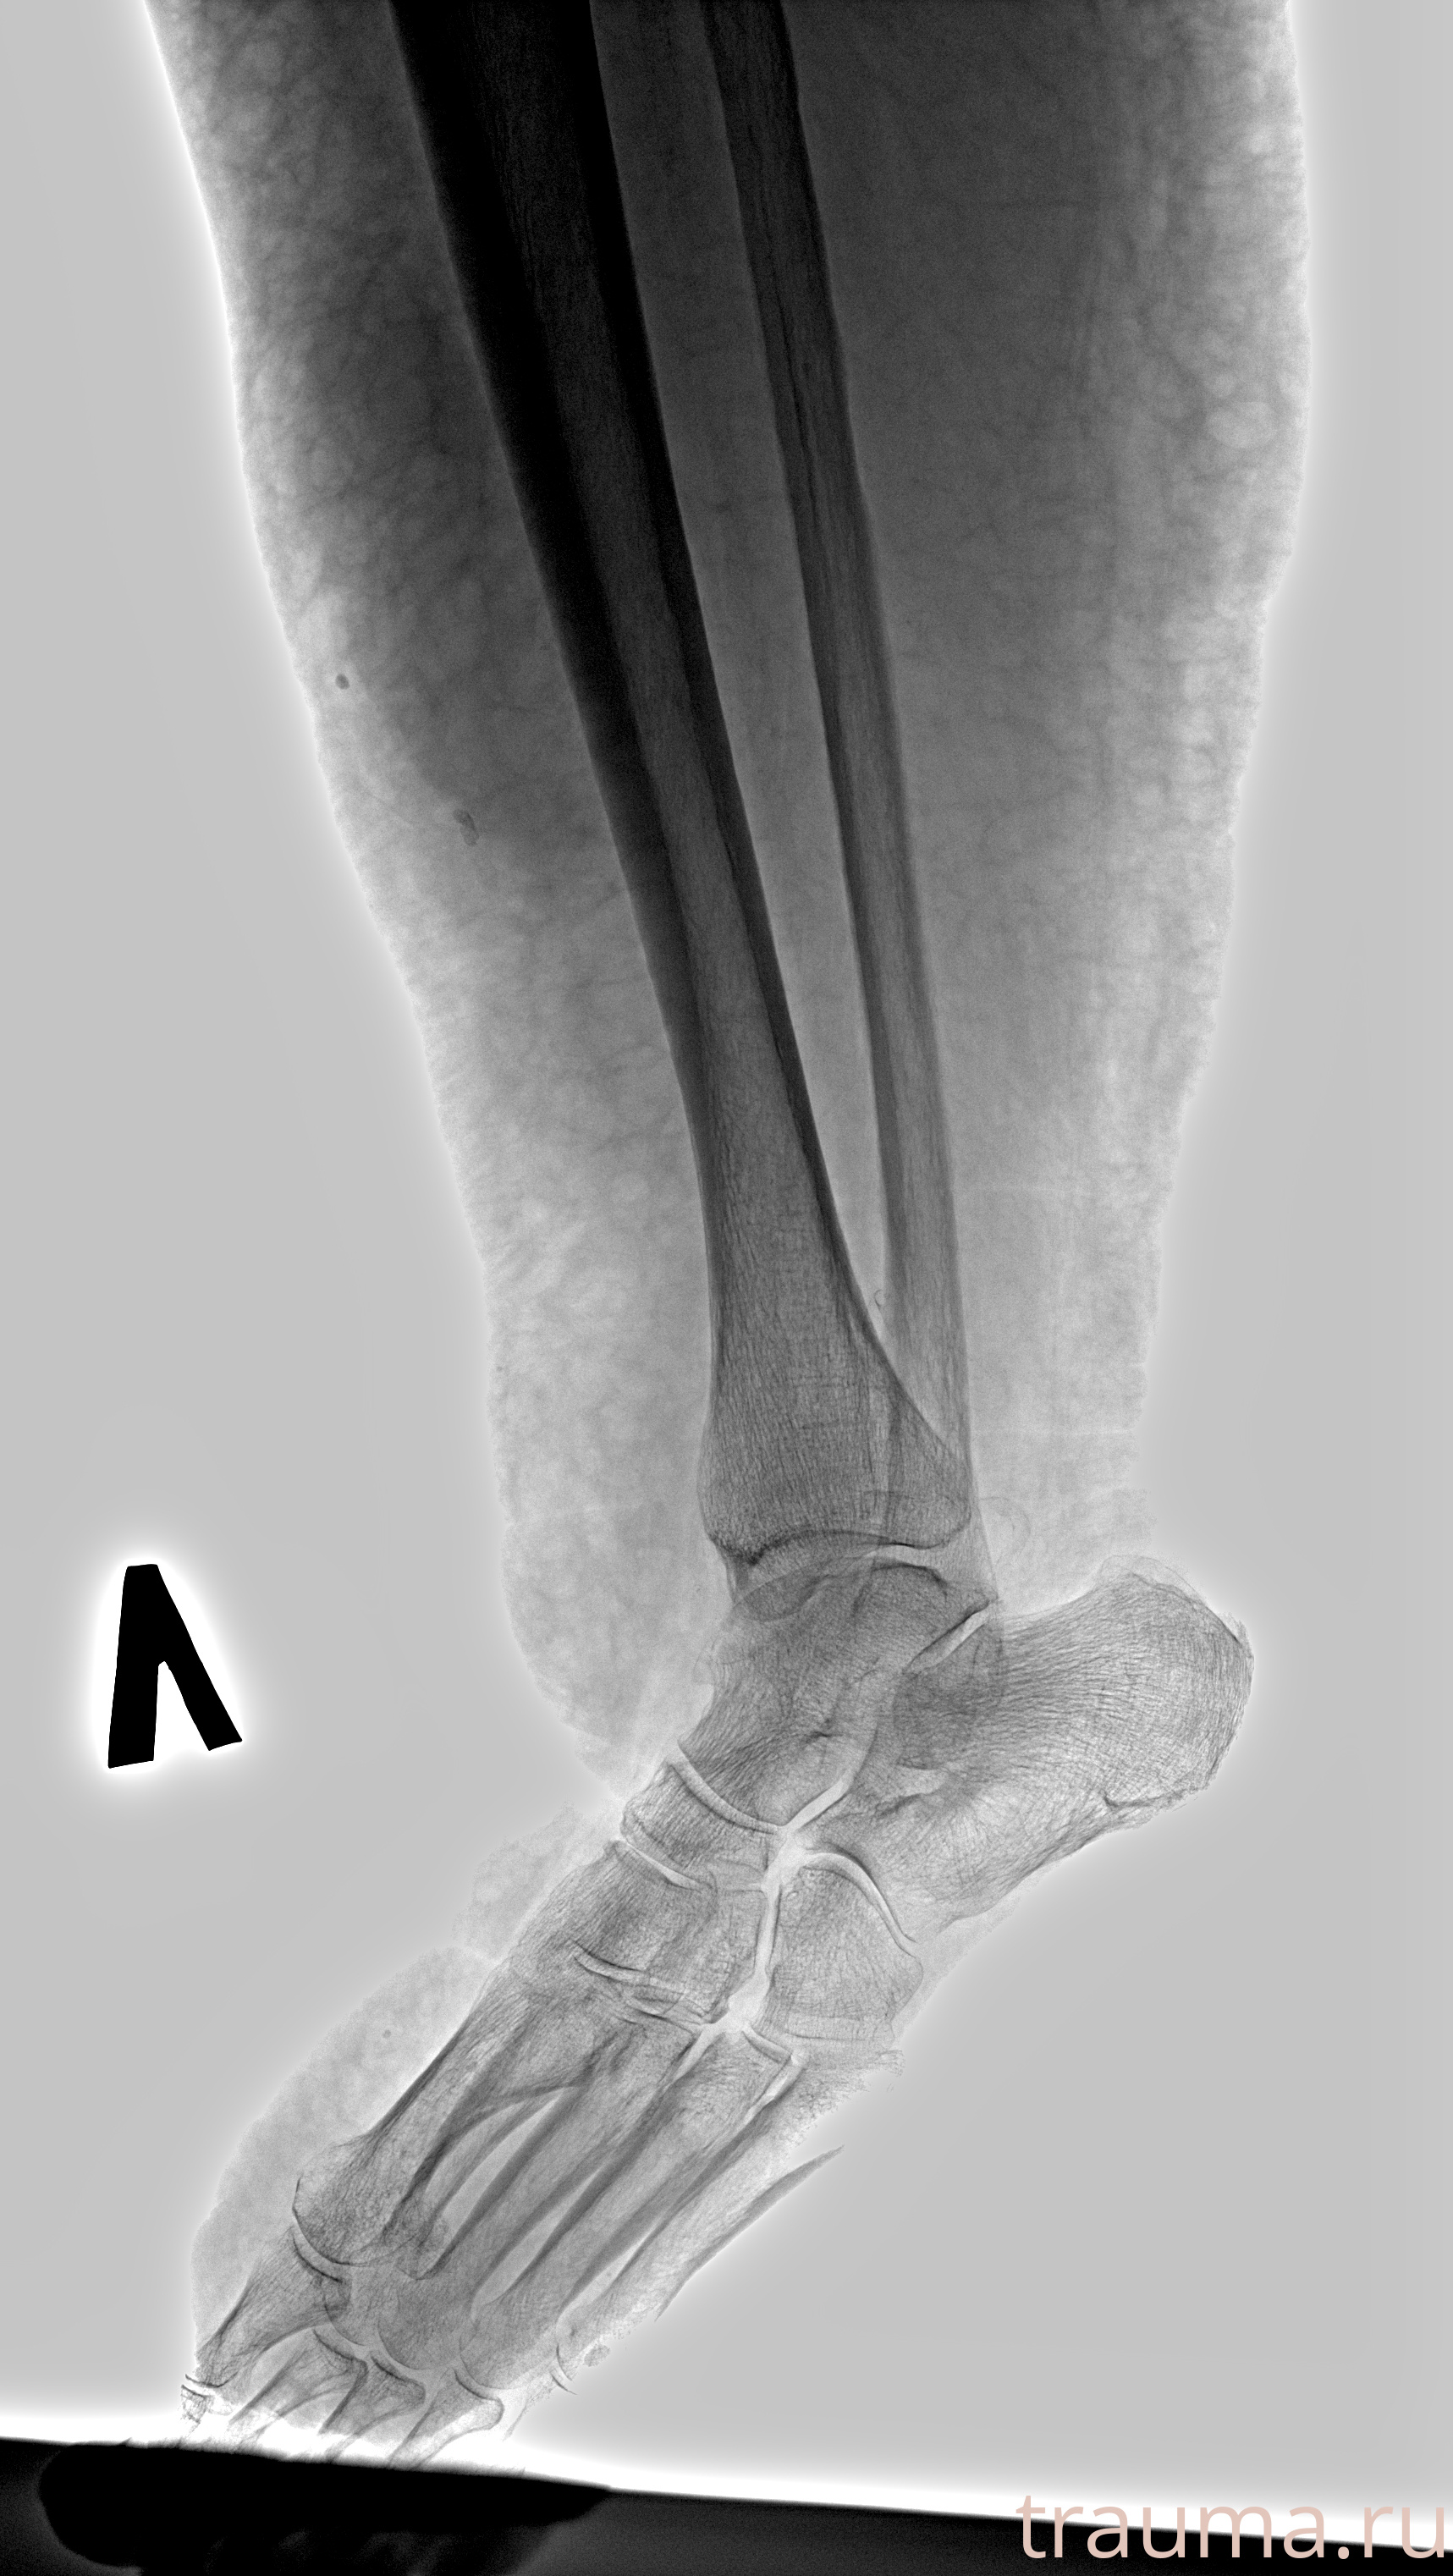

Рентген на дому: по вашему адресу приезжает врач-рентгенолог, травматолог-ортопед с мобильным рентгеновским аппаратом, проводит диагностику травмы или заболевания, делает необходимые рентгенограммы, дает рекомендации по дальнейшему лечению. Получить качественные снимки в домашних условиях возможно благодаря уникальной методике, разработанной МосРентген Центром для института  Склифосовского

при переломе шейки бедра и пневмонии от компании МосРентген Центр - партнера Института имени Склифосовского